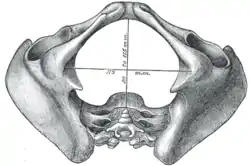

Diameters of pelvic inlet

Diameters of pelvic inlet Right hip bone. External surface.

A distinction is made between the lesser or true pelvis inferior to the terminal line, and the greater or false pelvis above it. The pelvic inlet or superior pelvic aperture, which leads into the lesser pelvis, is bordered by the promontory, the arcuate line of ilium, the iliopubic eminence, the pecten of the pubis, and the upper part of the pubic symphysis. The pelvic outlet or inferior pelvic aperture is the region between the subpubic angle or pubic arch, the ischial tuberosities and the coccyx. [3]

Alternatively, the pelvis is divided into three planes: the inlet, midplane, and outlet.[4]